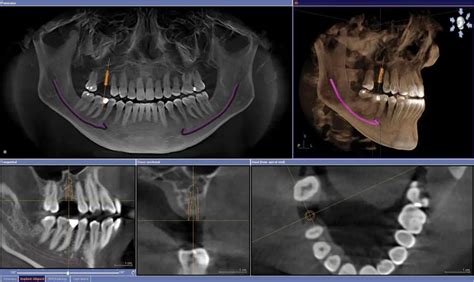

Tomografía Volumétrica en la Planificación de Tratamientos

El uso de la tomografía volumétrica se va incorporando cada vez con mayor aceptación por parte de los clínicos. La planificación de casos iniciales y del retratamiento convencional y quirúrgico con tomografía 3D, ha ayudado a la creación de conceptos y protocolos de aproximación mínimamente invasivos, con la consecuente disminución de desgastes innecesarios de estructura dentaria.

Si bien aún no existe una contundente evidencia científica que respalde estos protocolos, los estudios que van apareciendo sugieren que la estructura que se conserva va a favor de mantener a dientes más estable desde el punto de vista funcional.